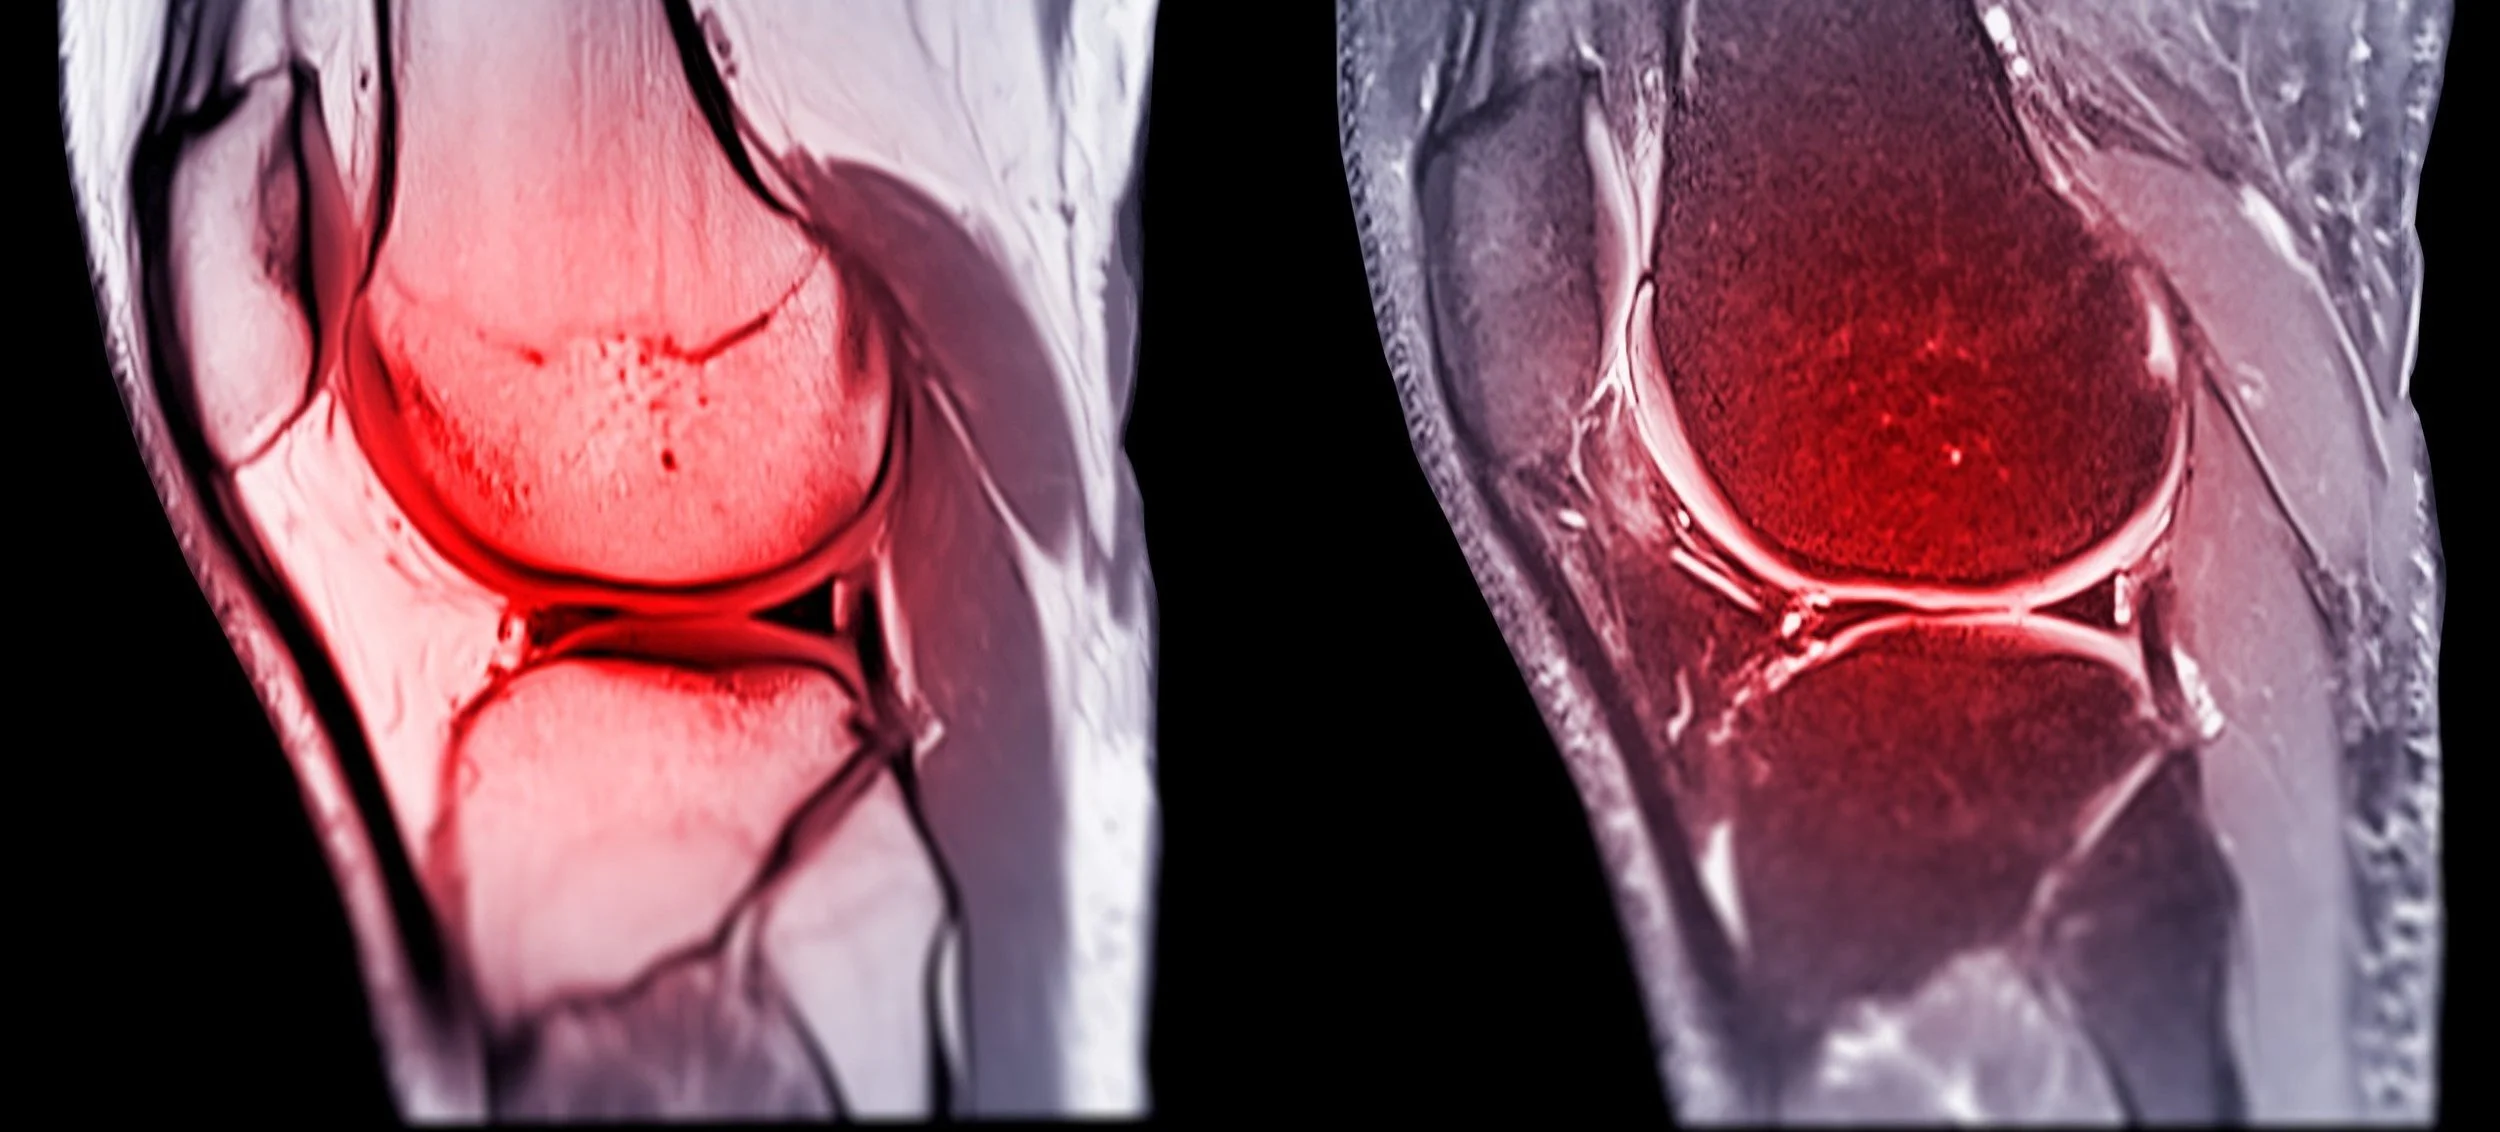

A medical professional viewing MRI scan images of a knee joint on a computer monitor in a clinical setting.

Musculoskeletal Imaging is a subspeciality of Radiology that looks at Joints, Muscles, Nerves and Bones. It encompasses Sports Imaging and Imaging of Degenerative changes in the body.